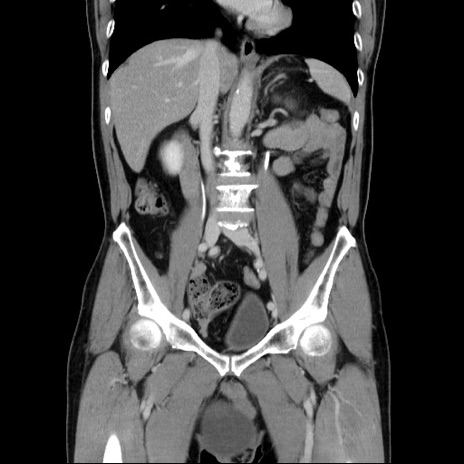

症例34(冠状断像)

【症例】60歳代 男性

【主訴】右鼠径部膨隆

【現病歴】1年程前より右鼠径部膨隆あり。自己にて還納可能だったため放置していた。3時間前より右鼠径部の脱出を認め、還納困難となり受診。

【既往歴】高血圧

【身体所見】右鼠径部に小児頭大の膨隆あり。弾性硬であり、用手還納は困難。左鼠径部にも膨隆を認める。脱出はなし。